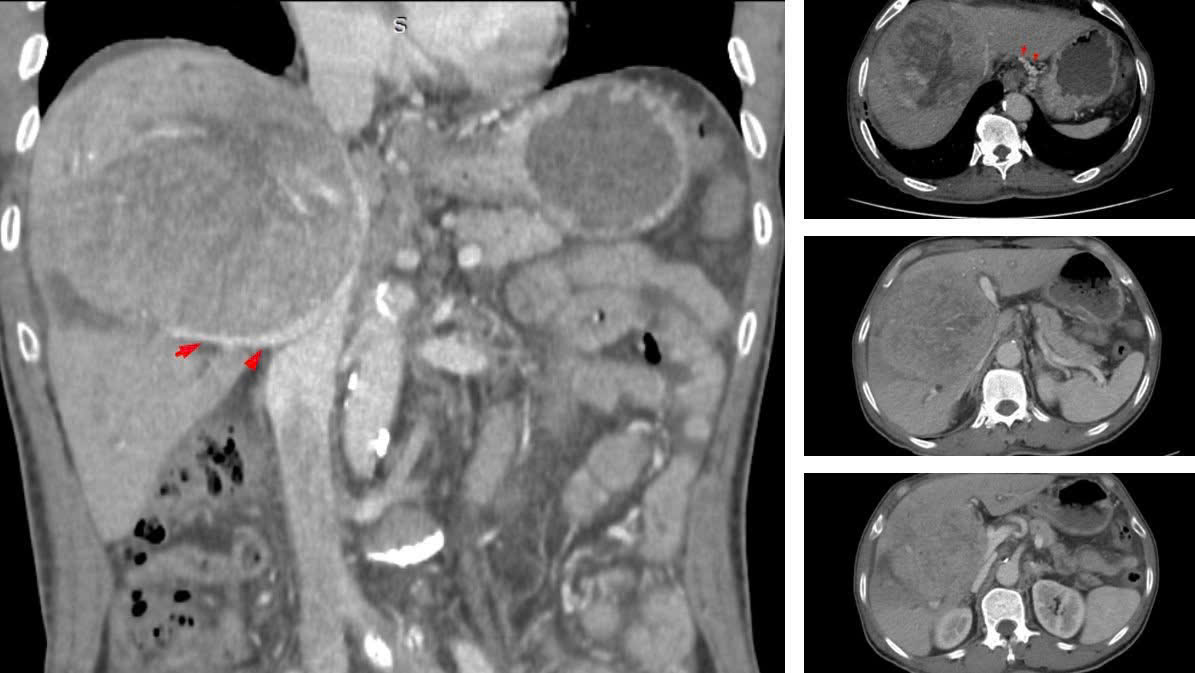

Chỉ đến khi triệu chứng rõ ràng, bệnh nhân mới đi kiểm tra, khối u gan đã phát triển với kích thước khổng lồ từ 10–12 cm. Tại một số cơ sở y tế, ông từng được tiên lượng thời gian sống không quá 9 tháng.

Tháng 7/2023 bệnh nhân có khối u gan kích thước lớn.

BSCKII Nguyễn Trường Giang, Phó Giám đốc Trung tâm Phẫu thuật Gan mật - Tiêu hóa (Bệnh viện Bệnh Nhiệt đới Trung ương) cho biết, khi nhập viện, đây là ca bệnh rất nặng. Khối u lớn chiếm gần hết nhu mô gan, chèn ép rốn gan và các mạch máu, gây cổ chướng nhẹ và phù hai chi dưới.